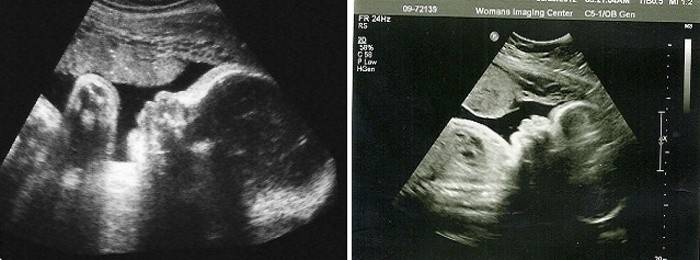

V tomto období zvyčajne nie je predpísaný ultrazvuk, ale pre zvláštne indikácie môže byť indikovaný ďalší výskum. Ak ste predtým podstúpili ultrazvuk, budete musieť vyhodnotiť všetky hlavné ukazovatele ultrazvuku - objasniť gestačný vek, odhadovanú hmotnosť a výšku plodu, zistiť pohlavie dieťaťa a tiež posúdiť stupeň jeho vývoja - ak v priebehu tehotenstva existujú nejaké odchýlky alebo odchýlky, či existujú vnútromaternicové telieska spomalenie rastu krbu.

Ultrazvuk je lekárom dešifrovaný - skúma sa štúdia, prezentácia plodu a poloha plodu, stav stien a krčka maternice, pupočníková šnúra, množstvo plodovej vody a umiestnenie, hrúbka placenty a jej stupeň zrelosti. Ak je to potrebné, predpíše sa ďalšia štúdia - dopplerometria toku krvi plodu, ktorá ukáže, ako aktívne plod dostáva výživu a kyslík. V tomto období je možné vykonávať 3D ultrazvuk, ale vzhľadom na veľkú veľkosť plodu ho nemôžete vidieť úplne na obrazovke monitora, môžete zobraziť iba jednotlivé časti.